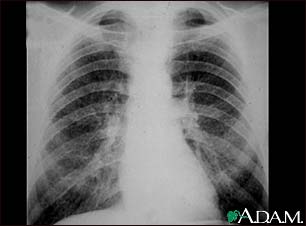

Coal workers pneumoconiosis - stage II

This chest x-ray shows stage II coal worker's pneumoconiosis (CWP). There are diffuse, small light areas on both sides of the lungs. Other diseases that may explain these x-ray findings include simple silicosis, disseminated tuberculosis, metastatic lung cancer, and other diffuse, infiltrative pulmonary diseases.